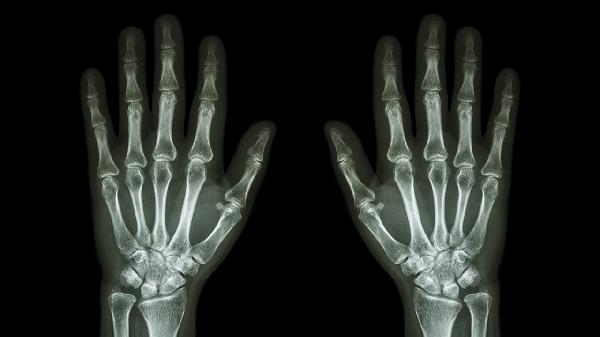

左手食指关节弯曲疼痛可能与关节劳损、腱鞘炎、骨关节炎、类风湿关节炎、痛风等原因有关,需要根据具体病因进行针对性治疗。

日常应注意手指的合理使用,避免长时间重复性动作,工作间隙适当活动手指关节。保持均衡饮食,控制体重减轻关节负担,适当补充富含钙质和维生素D的食物。如果关节疼痛持续不缓解或伴有明显肿胀、变形,应及时前往骨科或风湿免疫科就诊,通过X光、血液检查明确诊断,避免延误治疗导致关节功能受损。寒冷季节注意手部保暖,可佩戴手套减少寒冷刺激,适当进行手指伸展运动维持关节灵活性。